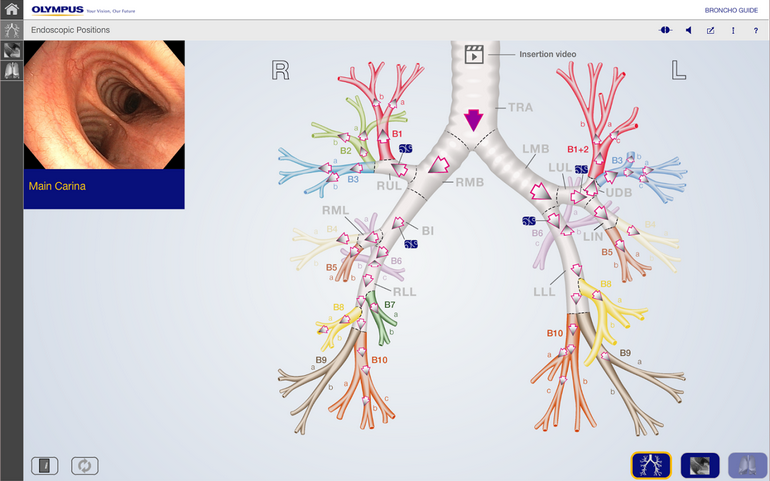

Вы выполняете, приближенное к реальности, обследование бронхиального дерева в HDTV качестве бронхоскопом BF-H190.

Реализована функция внутрипросветной эндонавигации по бронхиальному дереву!

Вы сможете последовательно начиная от карины, используя тачскрин, выбирать направление и изучать\вспоминать анатомию бронхиального дерев

Комментарии диктора статичных изображений и переходные видео применены для максимального облегчения пространственной ориентации и подробного объяснения о ангуляции и движении бронхоскопа во время исследования.ВИДЕО работы приложения можно посмотреть на сайте разработчика:

Anatomy training tool

You are welcome to experience a bronchoscopic examination, almost as if it were done in a real clinical setting. Starting at the main carina, this app enables you to steer a HDTV bronchoscope through the bronchial tree step-by-step, from one carina to the next. Audio commentated still images and transitional videos are displayed facilitating spatial orientation and providing detailed explanation about the angulation and movement of the bronchoscope. Highly experienced medical experts have been involved in the development of this training app; however, please keep the following aspects in mind: